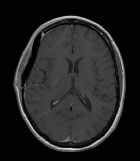

Un méningiome bien trop agressif…

Cancer du SNC

Cas Clinique

Source : NeuroScoop.net - Actu'Hebdo février 2016

Dr François-Xavier Ferracci CHU Rouen Charles-Nicolle - Rouen

Clinique

Patiente de 39 ans, droitière

ATCD : Thalassémie mineure, Asthme

Céphalées depuis 2 mois

Difficultés de concentration

Ralentissement psychomoteur

Désorientation temporelle